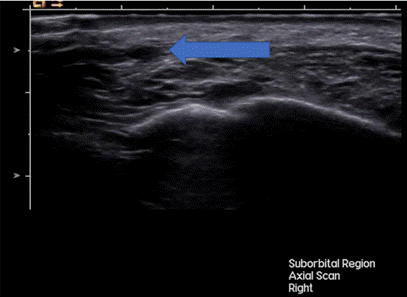

Для объективной количественной оценки динамики состояния гранулем и перифокальных мягких тканей до и после лечения оценивали локализацию, глубину, линейные размеры (длина, ширина, глубина), эхогенность, количество и плотность цветовых картограмм потоков в режиме цветового доплеровского кодирования (ЦДК), рассчитывали объем образований (гранулем) по формуле. Оценка данных параметров производилась до курса терапии и спустя 1 месяц (сразу после завершения курса терапии). Повторная оценка проводилась по тем же параметрам, в той же проекции. Для уменьшения межоператорских ошибок все ультразвуковые исследования осуществлялись опытным специалистом, данные фиксировались в цифровом архиве. Результаты ультразвукового исследования до и после лечения наглядно продемонстрировали признаки регресса гранулем. При исходных УЗИ визуализировались гипоэхогенные или смешанной эхогенности образования неоднородной структуры, по большей мере - с нечеткими относительно ровными и неровными контурами, расположенные в дерме и/или подкожной жировой клетчатке (рис. 2).

Рис. 2. Ультразвуковая картина гранулемы инфраорбитальной области до проведения курса плазмотерапии. Составлено авторами по результатам данного исследования

Синей стрелкой указано овоидное неоднородно гипоэхогенное образование с относительно ровными нечеткими контурами (аппарат Siemens Acuson Sequoia, линейный датчик 17 МГц, режим серой шкалы (B-режим)).

Средний наибольший исходный размер составил 8,4 ± 2,1 мм. В режиме ЦДК в 68% гранулем регистрировался периферический или интранодулярный тип распределения цветовых картограмм потоков различной степени интенсивности, что могло соответствовать сосудистым реакциям вследствие воспалительного процесса.